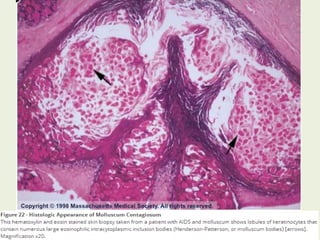

• The cellular proliferation produces lobulated epidermal

growths which compress the papillae until they appear as

fibrous septa between the lobules, which are pear shaped

with the apex upwards.

• Basal layer remains intact.

• Cells at the core of the lesion show the greatest distortion

and are ultimately destroyed, and appear as large hyaline

bodies (Molluscum bodies/ Henderson-Patterson Bodies)

containing cytoplasmic masses of virus material.

Lobular Epidermal

growths

Molluscum Bodies

Compressed dermis

Basement Membrane Intact

Histopathology of Molluscum

Contagiosum:

Pathology: • The virusenters the basal epidermis causing an increase in cell division extending into the suprabasal layer. • The cellular proliferation produces lobulated epidermal growths which compress the papillae until they appear as fibrous septa between the lobules, which are pear shaped with the apex upwards. • Basal layer remains intact. • Cells at the core of the lesion show the greatest distortion and are ultimately destroyed, and appear as large hyaline bodies (Molluscum bodies/ Henderson-Patterson Bodies) containing cytoplasmic masses of virus material. • Inflammatory changes in the dermis are absent or slight. • Lesions of long duration: may exhibit chronic granulomatous infiltrate due to the discharge into the dermis of the contents of a papule . • In spontaneous regression: the lesions are surrounded by an infiltrate of interferon‐producing plasmacytoid dendritic cells.

Lobular Epidermal growths Molluscum Bodies Compresseddermis Basement Membrane Intact Histopathology of Molluscum Contagiosum: